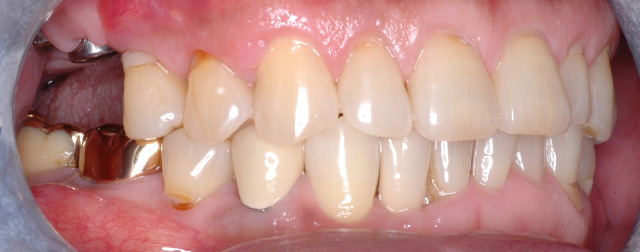

50대 남성분의 치아 사진입니다.

앞니도 고르고 겉으로 봐서는 특별한 문제가 없어 보입니다. (3년전 사진)